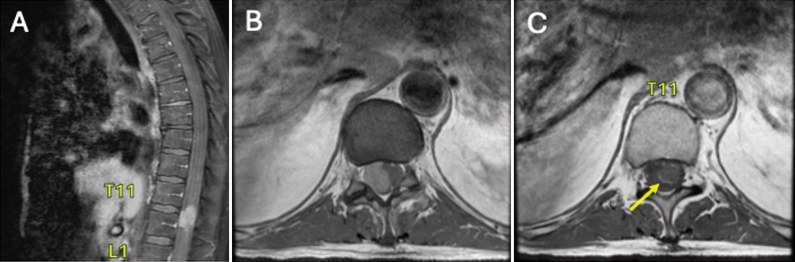

Observations: The authors describe the case of a 74-year-old male who presented with back pain, lower extremity weakness, and numbness. MRI revealed a contrast-enhancing intradural, extramedullary lesion at T11-12 with a hypointense signal on T2-weighted imaging. The patient underwent resection of the lesion. The diagnosis of primary spinal melanoma was confirmed by histopathology, immunohistochemical studies, and lack of primary lesions on dermatological and ophthalmological examination. Next-generation sequencing also revealed a guanine-nucleotide binding protein (GNAQ) mutation.